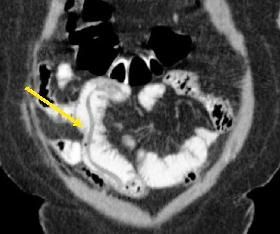

Treatment was initiated with ciprofloxacin and flagyl for a presumed infectious colitis. Because of the cecal findings, the patient was admitted for possible appendicitis. Results of a subsequent CT scan showed large worms in the distal jejunum and ileum (Figures 1-4). Stool samples were sent for an ova and parasite (O&P) test. The patient improved and was discharged home.

Figure 1